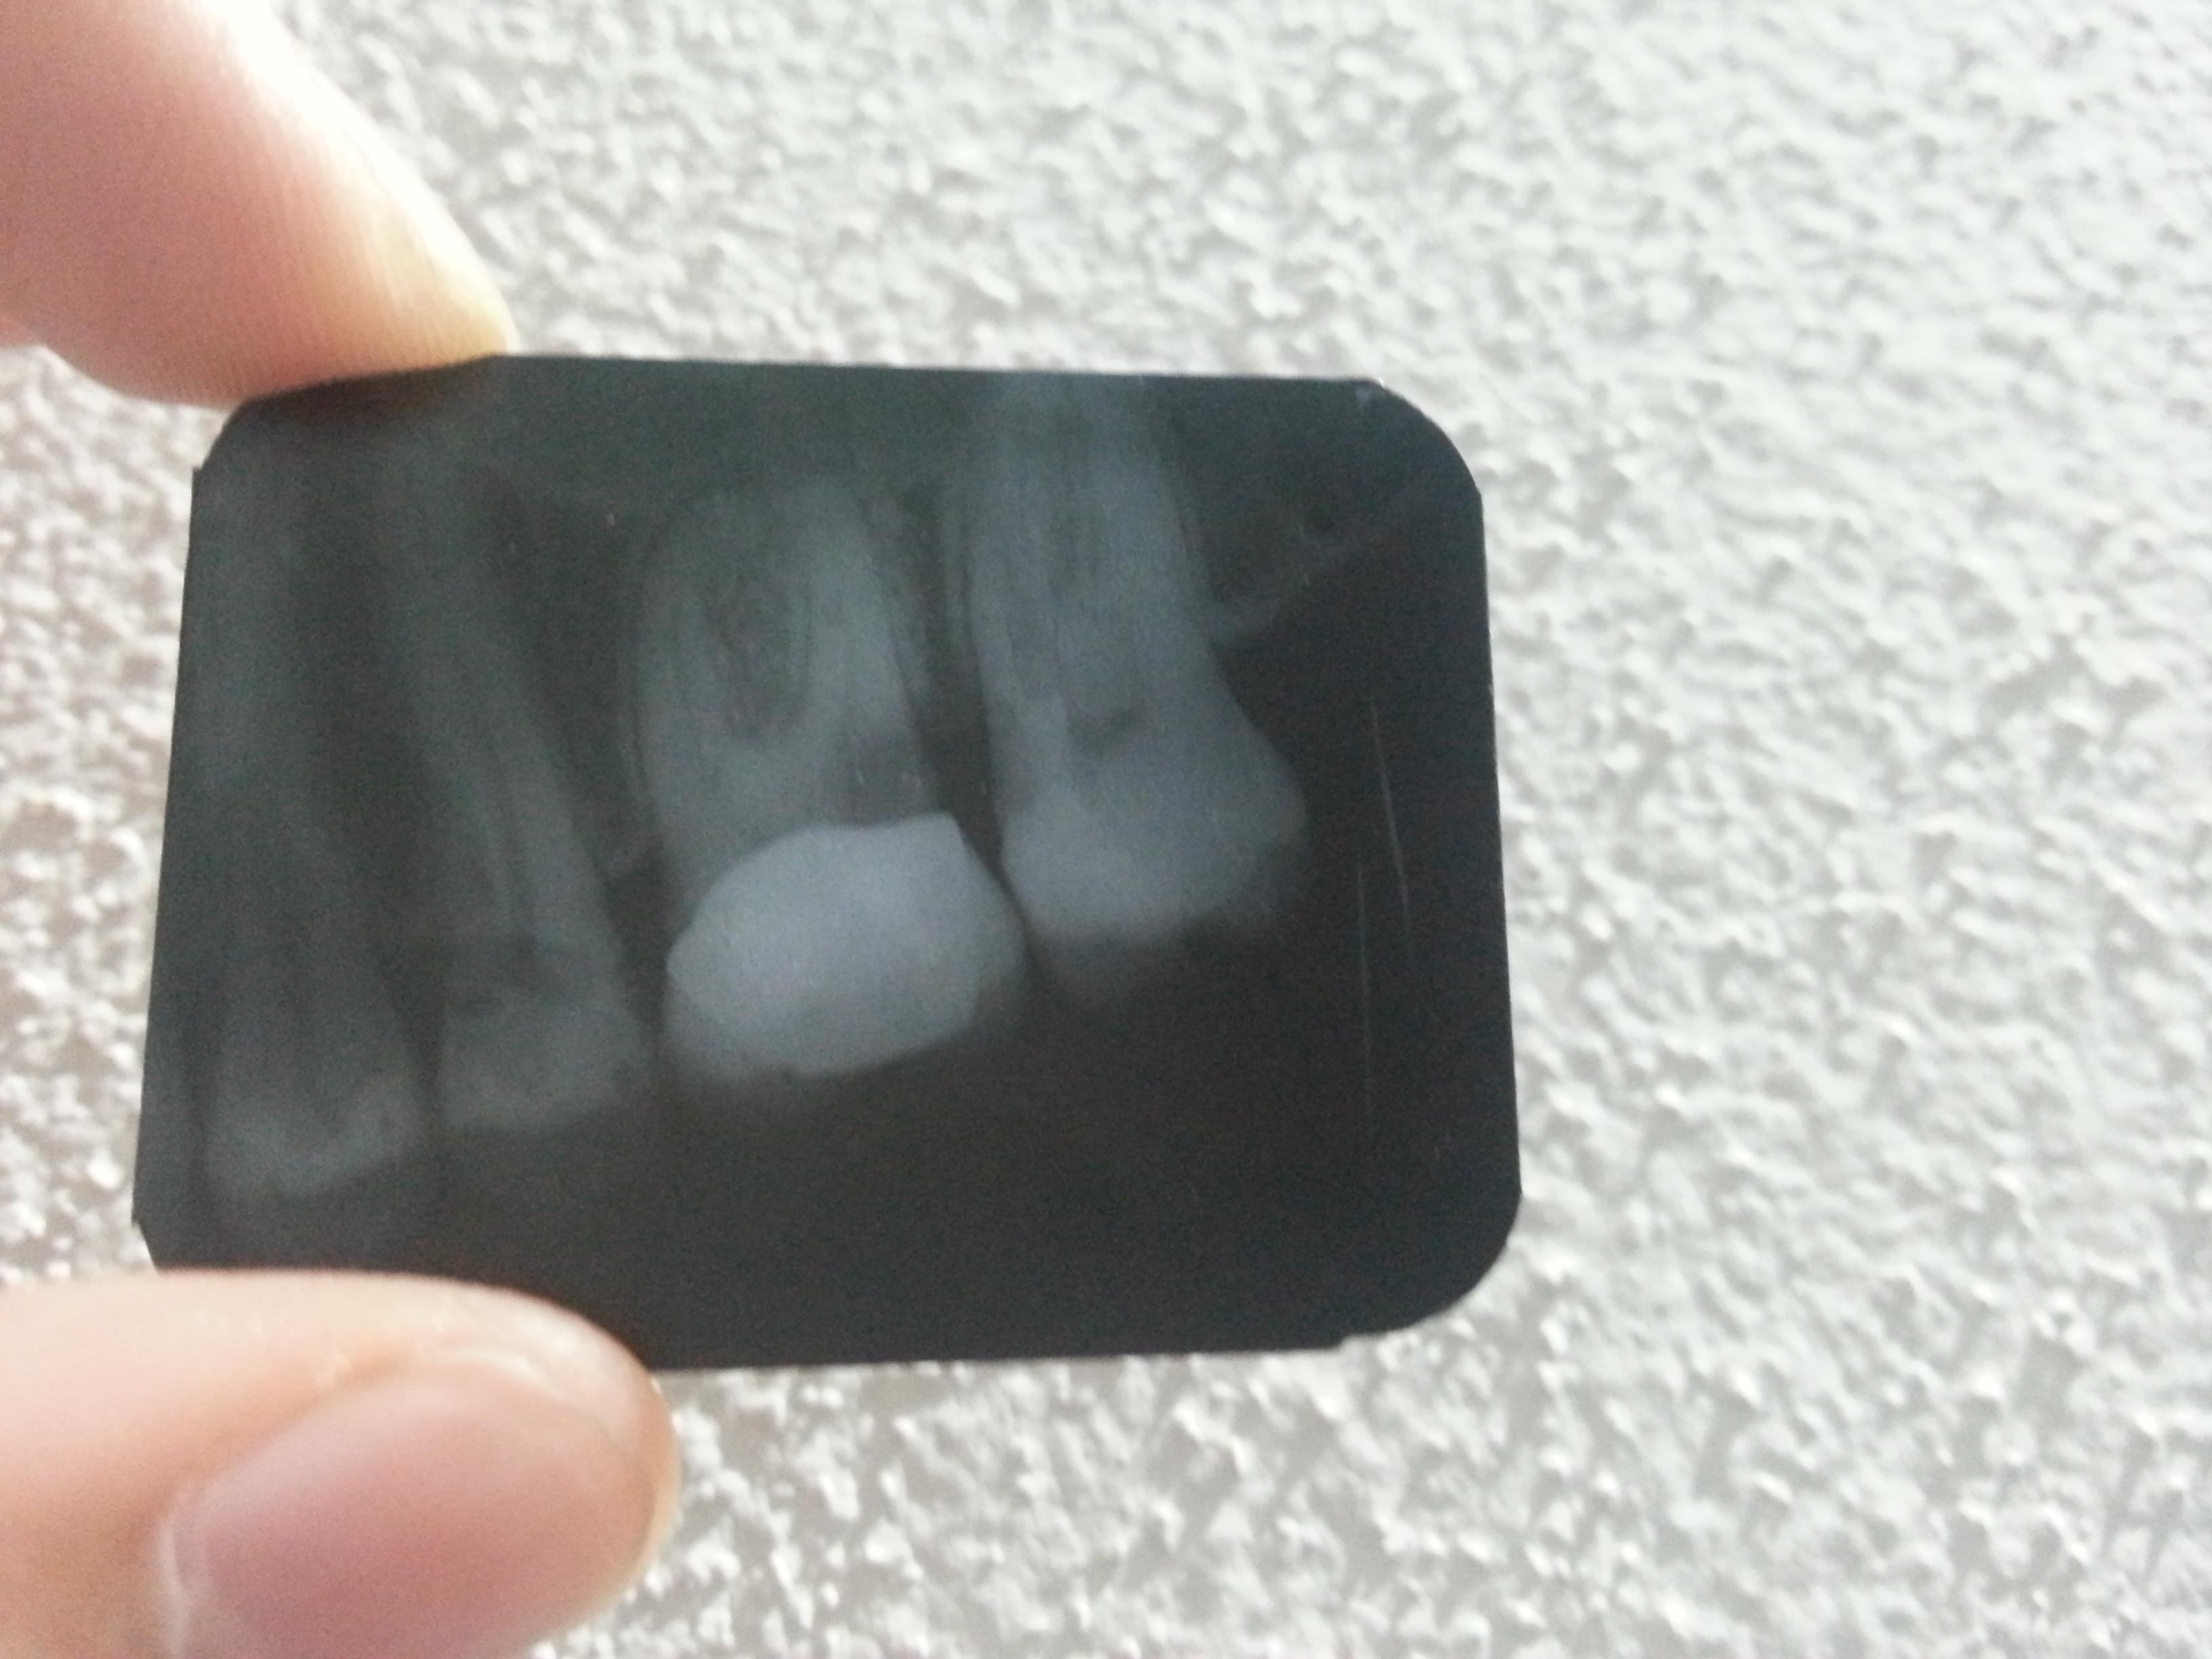

rx

..Gentilissimo dott.Piana, la ringrazio per la sua velocissima risposta. Questa rx è lunica vosa che ho, mi è stata fatta a luglio nello studio. Ho 30 anni e purtroppo non ho una buona storia dentale. Curo i denti da quando sono bambina, causa carie estese e dopo aver messo l’apparecchio per denti storti e mal occlusione la cosa è peggiorata dal posizionamento dell’espansore.

Spero che questa radiografia sia precedente alle cure!…Comunque NON si tratta di patologia della biforcazione che comunque alla sua età e praticamente assente. Invece è chiaro che questo dente deve essere devitalizzato (bene) immediatamente perchè la carie tocca ormai la parte vitale. La corona va rifatta preceduta però da un perno moncone ben fatto.

Corona e carie